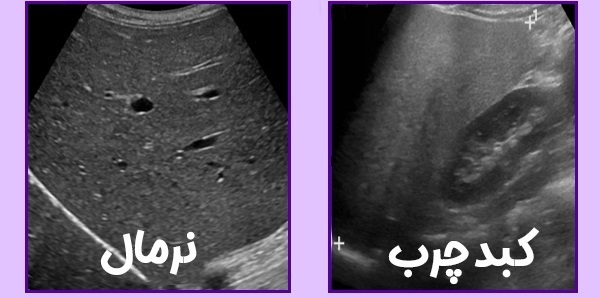

سونوگرافی: یکی از رایجترین روشها برای شناسایی تجمع چربی در کبد

کبد چرب در اثر تجمع چربی در سلولهای کبد ایجاد میشود. این بیماری معمولاً در چهار گرید طبقهبندی میشود که هر کدام ویژگیها و علائم خاصی دارند.